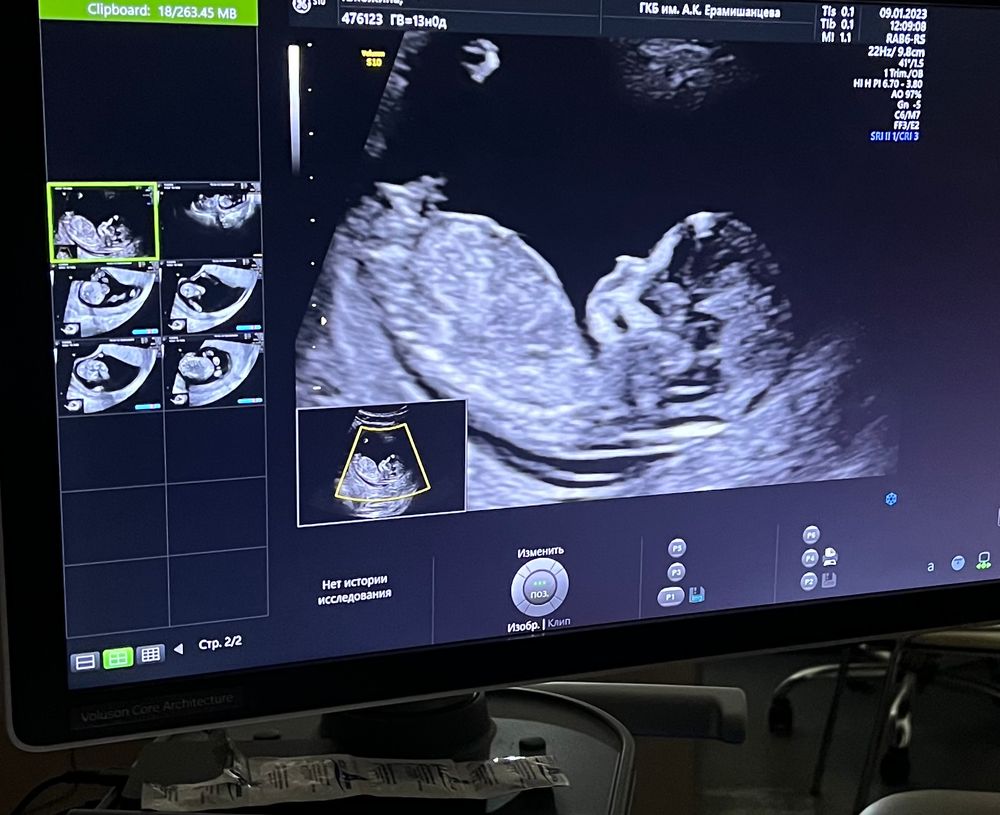

Видно ли пол?🤔

Неть, не видно:)

На этом снимке не видно половой бугорок.

Евгения, ну, недели через 3 можете ещё раз сходить - там уже всё точно будет видно))

Пол не видно должно быть, а врач, который проводит исследование, видит железы и определяет мужские они или женские.